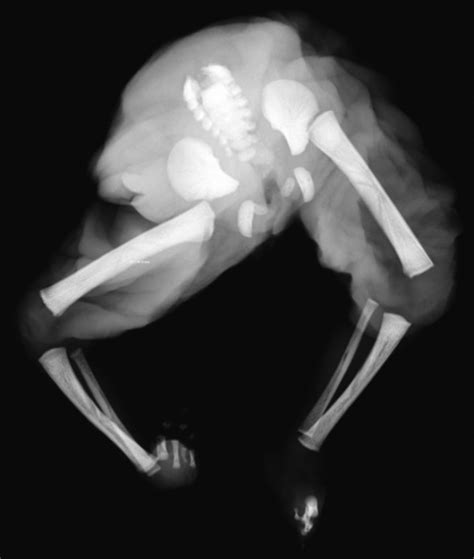

• Abnormal development of the acardiac twin, often characterized by a lack of a functional heart and other organ malformations.

TRAP sequence poses significant risks and complications for both twins. The pump twin is at high risk of developing high-output cardiac failure, which can lead to hydrops fetalis, a condition characterized by abnormal fluid accumulation in the fetus. Other potential complications include: